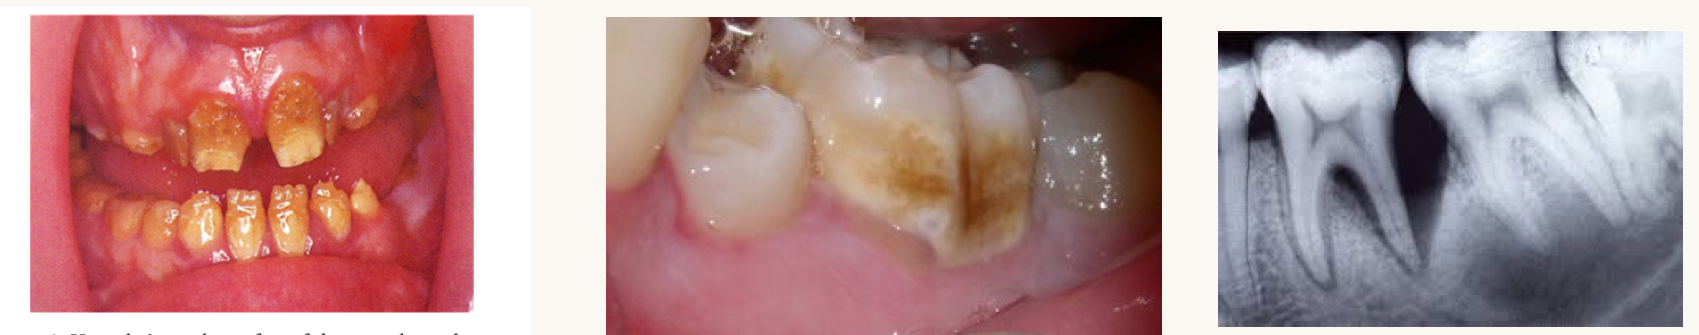

what is this condition and what vitamins is this person likely deficient in?

severe hypoplasia, hypocalcification, alveolar bone loss, delayed tooth eruption

vitamin D

what is this condition and what mineral is this person likely deficient in?

brittle bones leading to chips/fractures, increased risk of decay and caries

calcium

fluoride deficiency

fluoride

excess fluoride can causes fluorosis